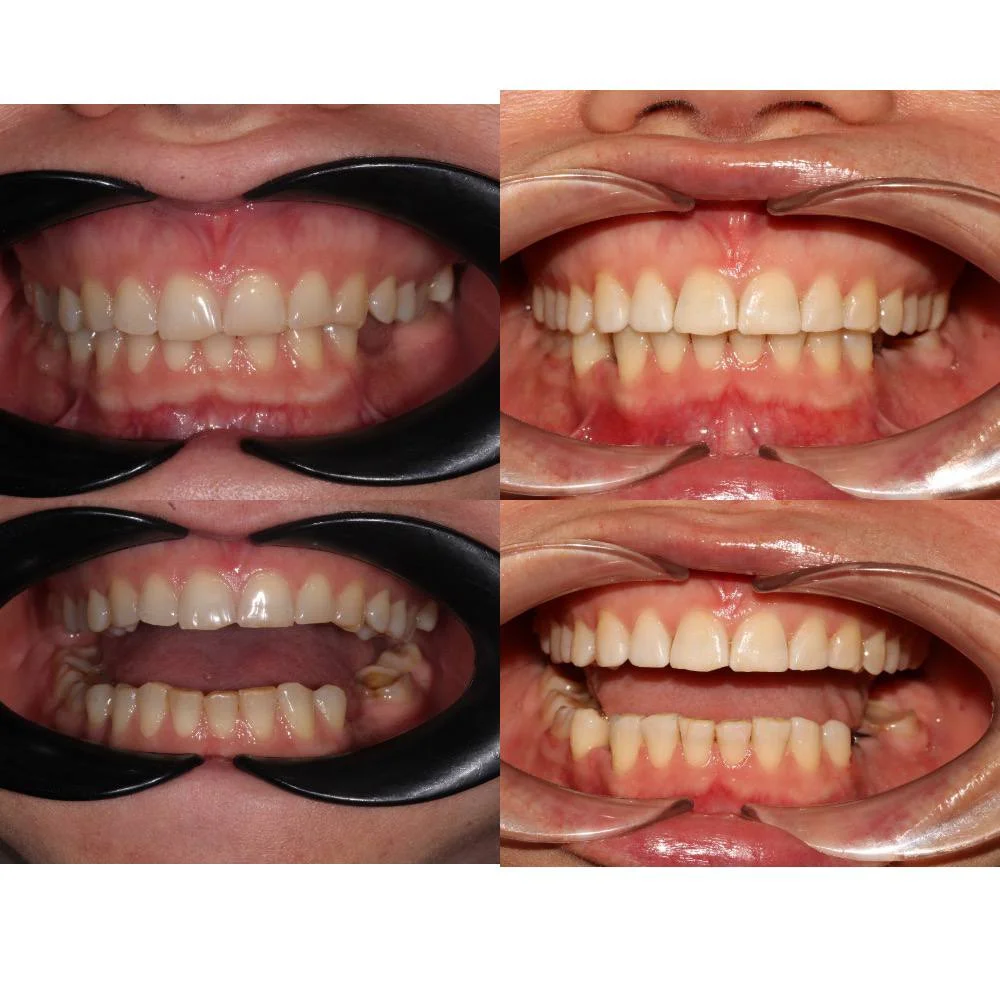

Проблема: Пациентка обратилась с жалобами на неровные зубы и неправильный прикус. Челюсти смыкались некорректно, зубы стояли со смещением. Часть зубов нуждалась в восстановлении коронками, но ставить их на кривой ряд с неправильным прикусом значит заведомо сократить им срок службы. Нагрузка будет распределяться неравномерно, и конструкции быстро выйдут из строя. Поэтому первый этап — ортодонтия, второй — протезирование.

Решение: Установили металлические самолигирующие брекеты H4 на обе челюсти. За 28 месяцев выровняли зубы и привели прикус в норму. После снятия брекетов зафиксировали ретейнеры на обе челюсти. Пациентка направлена к ортопеду — в течение недели устанавливает коронки, после чего будет проведено сканирование и изготовлены ретенционные капы уже по окончательному контуру зубов.

Двухэтапный случай: сначала ортодонтия, потом протезирование. Ставить коронки при неправильном прикусе нельзя — нагрузка ляжет неравномерно, конструкции не прослужат долго. Брекеты H4 отработали за 28 месяцев, ряд подготовлен. Ретенционные капы сознательно делаем после коронок — контур зубов изменится, и капы должны соответствовать финальному результату.